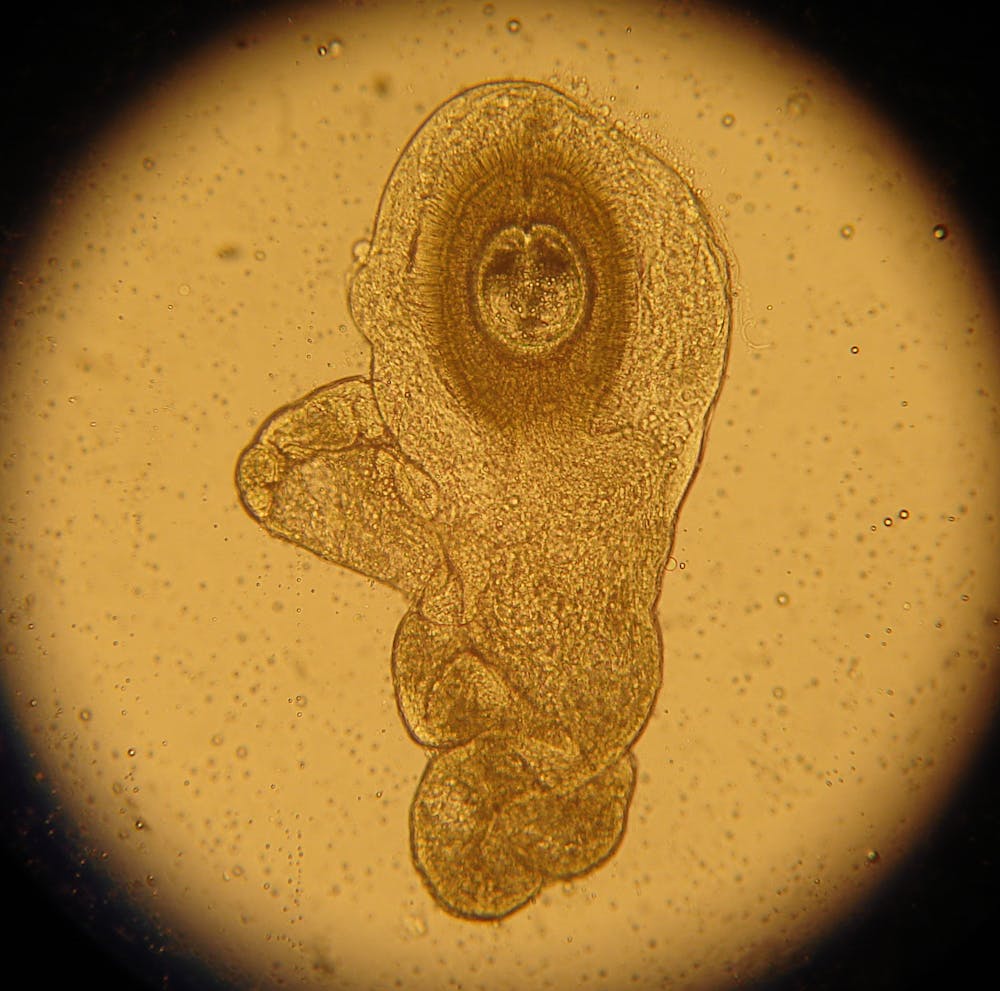

Parasites In Tissue How To Identify The Structures Cap Today

Practical Guidance For Clinical Microbiology Laboratories Laboratory Diagnosis Of Parasites From The Gastrointestinal Tract Clinical Microbiology Reviews

Creepy Dreadful Wonderful Parasites Answer To Case 273